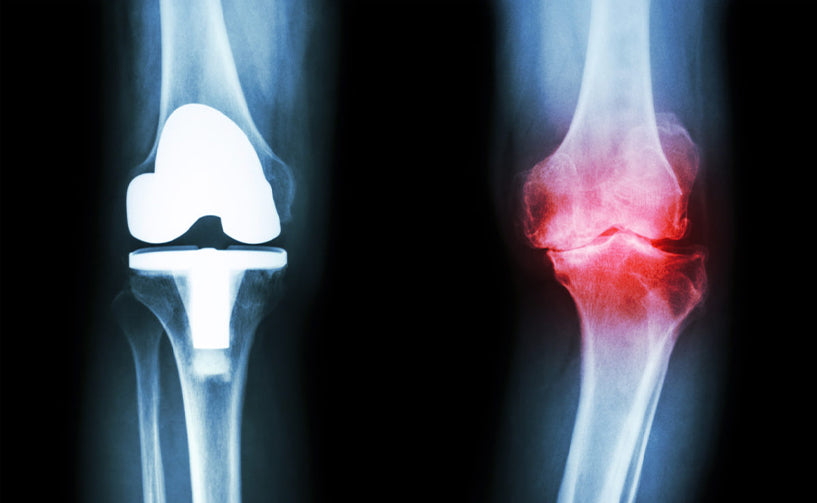

Osteoarthritis is a form of arthritis that results in the breakdown of cartilage or flexible tissues in joints. It is a disorder that primarily affects the joints of the body due to wear and tear of cartilage which is responsible for protecting the joints. When the cartilage wears out, the bones become pitted and rough leading to pain.

A healthy joint is protected by a synovial membrane which excretes synovial fluid. Damage to the membrane hampers the functioning of the synovia fluid and causes inflammation. Osteoarthritis is caused by ageing, injury, chronic joint problem or is heredity. It is characterised by inflammation of joints, pain and stiffness and is quite common among aged people.

It is not an autoimmune disease, unlike rheumatoid arthritis. It can affect joints of thumbs, knees, back, hips and legs. This disorder is common in both men and women. Some common names of osteoarthritis are degenerative joint disease and degenerative arthritis.